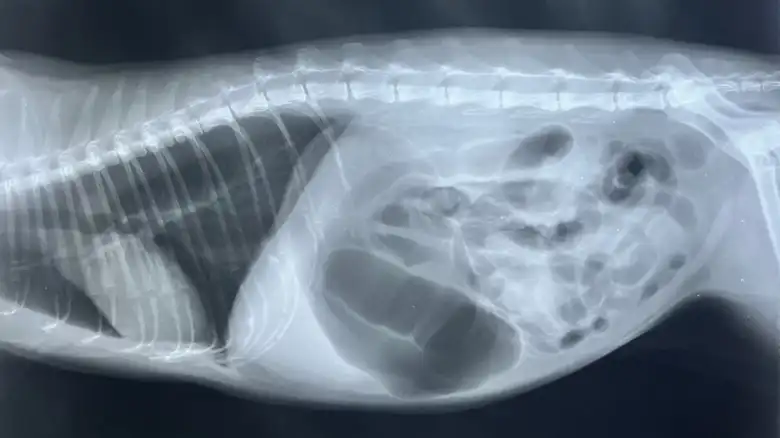

6. Gastric dilatation volvulus treatment - $500 - $10,000

wimala namket/Shutterstock

Gastric dilatation-volvulus, often called bloat, occurs when the stomach fills with gas, fluid, or food, causing it to expand and potentially twist. Bloat in dogs is dangerous and requires immediate veterinarian intervention, as the twisting can cut off blood supply to various organs, leading to numerous complications, shock, and death. This condition primarily affects large dog breeds, with great Danes having a high occurrence rate of bloat at around 39% (via Animal Emergency Hospital). GDV can also occur in cats, but the condition is extremely rare, with only a handful of cases ever reported.

The cost of treating gastric dilatation volvulus can range from $500 to $10,000 depending on the severity and if surgery for GDV can be prevented through other measures taken by a vet, according to Wag!. However, expect a bill upwards of $6,000 with no guarantee of success. In emergencies, your vet may also perform a gastropexy. However, this surgery, which involves creating permanent adhesion between the stomach and the abdominal wall to prevent twisting in the future, can be done in advance. If you have a canine prone to the condition, you can often have the preventative surgery done at the same time as a spay or neuter or around one year of age; great Danes who got the surgery were around 30 times less likely to experience GDV later in life, per a 2003 study published in Preventive Veterinary Medicine. The cost of preventive gastropexy can be 2.5 times less than an emergency procedure.